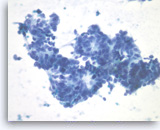

Ductal adenocarcinoma #1,

Pancreas FNA, Direct Smear.

The aspirates show single and clusters of malignant epithelial cells. The clusters are three-dimensional with overlapped nuclei. A few histiocytes are seen in the background.

20X